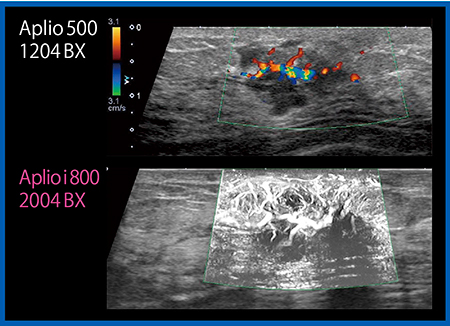

新機能紹介

Aplio iシリーズには,新しい機能として,フリーハンドでスキャンした範囲の情報をつなげて立体的に画像を再構築する技術“Smart Sensor 3D”が搭載された。これまでも4Dプローブを用いて限られた範囲の3D画像を再構成することはできたが,24MHzのPLI-2004BXにより,高周波リニアプローブで3D画像を得ることができるようになった。Smart Sensor 3Dではスキャンデータをボクセルデータとして保存して,冠状断や頭尾方向の3D画像を再構成し,皮膚を透かして見るように,コントラストが異なる部分が浮き立ったShadow Glass画像を観察することができる(図12 右下)。再構成した画像は,光源の位置を変えたり回転したりするなど,任意に観察が可能である。検査をしながらその場で再構成画像を表示できるため,3D画像を回転して腫瘤の範囲を確認するなど,活用範囲が広がるかもしれない。

図12 Shadow Glass画像(右下)